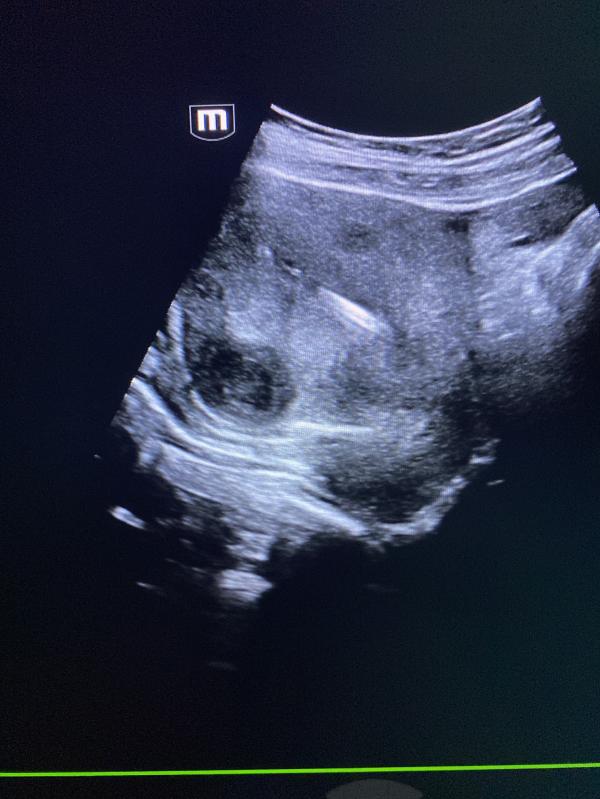

Узи миома матки: можно ли увидеть миому на снимке УЗИ? Случаи миомы и камней в почках

Можете на узи снимке увидеть миому матки?

Сегодня было много миом .